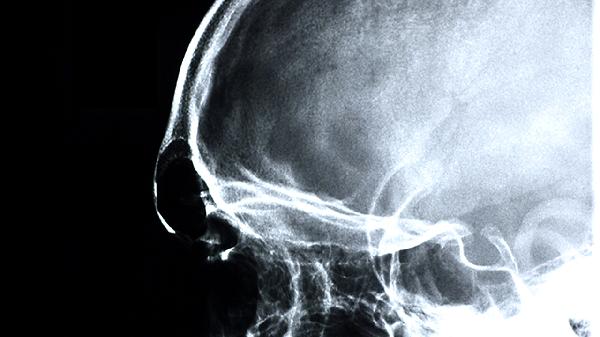

胎儿脑膨出通常由神经管闭合不全引起,主要与遗传因素、叶酸缺乏、环境致畸物暴露、病毒感染、代谢异常等因素有关。胎儿脑膨出属于先天性神经系统发育异常,表现为部分脑组织通过颅骨缺损处向外突出。